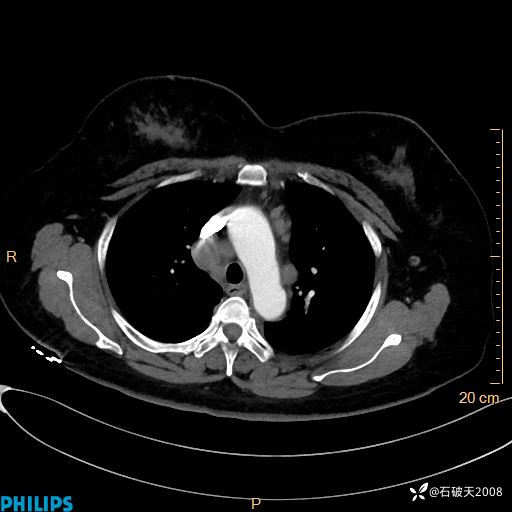

肺结节病?纵膈型肺癌?淋巴瘤?有点意思,欢迎围观

女 52岁 主 诉:咳嗽10余天,咳痰2天。

现病史:10余天前无明显诱因出现咳嗽,呈阵发性干咳,伴咽喉部发痒,无咽痛,无咳痰,无鼻塞、流涕、打喷嚏,无发热、畏寒、寒颤,无头痛、头晕,无胸闷、胸痛,无反酸、烧心,无腹痛、腹泻,无尿频、尿急,无皮疹等,在当地诊所求治,给予口服药物治疗(具体不详),病情无好转。遂在当地社区卫生服务中心开具口服药物治疗(具体不详),疗效欠佳。2天前出现咳痰,在我院门诊求治,行胸部CT提示肺部感染,建议住院,患者要求口服药物治疗,目前仍咳嗽、咳白色粘痰,白天量多,夜间自觉喉部喘鸣音,遂再次来院就诊,以“肺部感染”为诊断收入院。发病以来,神志清,精神可,饮食可,夜间睡眠差,大小便正常,近期体重无明显变化。

纵隔窗